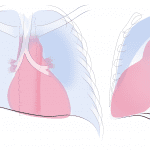

- Left upper lobe collapse with an aerated portion of the superior segment of the left lower lobe interposed between the atelectatic left upper lobe and the mediastinum (Luftsichel sign)

- Left upper lobe collapse